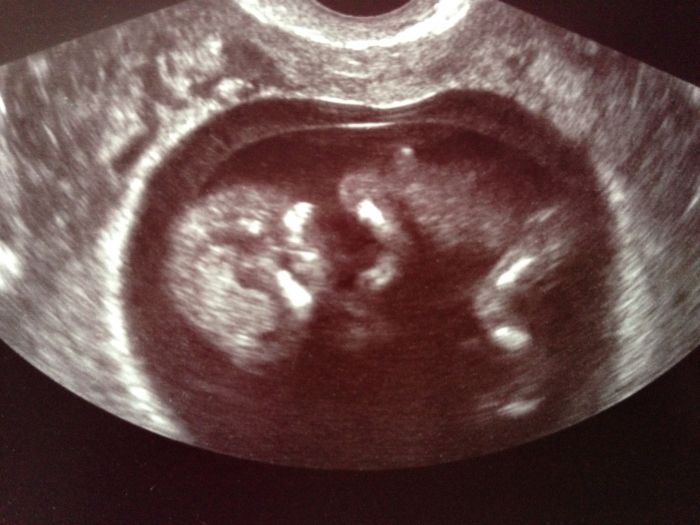

Ahoj holky :-)) tak mám za sebou utz ve 13tt ;-) jsme zdravý, žádné deformace ani roštepy :-)) mimísek sebou házel a mával mi :-) až sem musela zadržovat slzy :-)) přikládám fotečku :-))